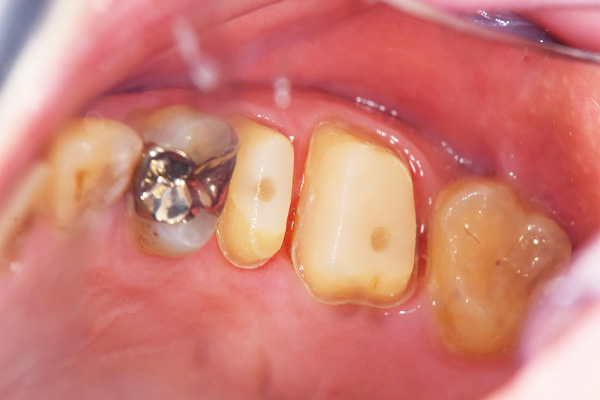

インレー症例

初診時パノラマ

初診時口腔内写真

iTero NIRI機能による診査

虫歯除去後

初診時バイトウィングデンタル

レントゲンだとちょっと虫歯が怪しいくらいに写っている。これだけだと確定診断としては、判断材料が少ないと考えられる。

黄色丸の部位が、他の部位と違って白く抜けがあるのがわかります。これがNIRI機能による虫歯の診査です。

この機能のおかげで、歯と歯の間の見つけにくい虫歯がよくわかるようになってきました。

In(インレー)セット後

当院では自費のインレー(つめ物)の場合、ゴムのシートをかけてから詰めていきます。

ゴムのシートをすることで、歯面を最大限乾燥することができ、接着力が上がる他、操作時の材料の誤飲の防止、接着剤の歯肉縁下(歯ぐきの中)への侵入を防止するなどといったメリットがあります。(歯の並びによっては、ゴムのシートができないことがあります。また、シートをかけることで苦しくなる、苦手という方には無理に行いません。)

年齢・性別 40代・男性

主訴 左上の奥歯がしみることがある

治療内容 左上4の虫歯

治療期間 2週間

リスク・副作用 虫歯の大きさによっては、神経をとらないといけなくなることがあります。

また、虫歯が大きかったケースで神経を残した場合、治療後にしみるなどの

症状が続くことがあります。

費用 ・ジルコニアインレーで修復

55,000円

治療方針

IOSのNIRI機能によって虫歯部分が明らかになったので、虫歯を除去後に修復治療を行うこととしました。

特記事項

ラバーダムは歯とつめ物をくっつける際に非常に効果的です。

人間は呼吸をしますので、お口の中はかなり湿度が高くなっています。水が多い状態でものをくっつけようと思ってもなかなかくっつかないということと同じになります。

ですので、呼気中の湿度に左右されないようにするために、ラバーダムを用いて接着力を高くしています。

ラバーダムで息が苦しくなる場合は使用しませんし、ラバーのアレルギーがある場合も使用できません。

担当医師所見

虫歯の有無を確認する上で今まではレントゲンと自分の目での確認でした。現在は目で見るよりもはるかにわかりやすいIOSという装置がありますので、虫歯の発見がしやすくなりました。

そのため、患者さんの虫歯の進行の段階が早いうちにわかる様になり、神経をとらなければならないというケースが非常に少なくなっています。